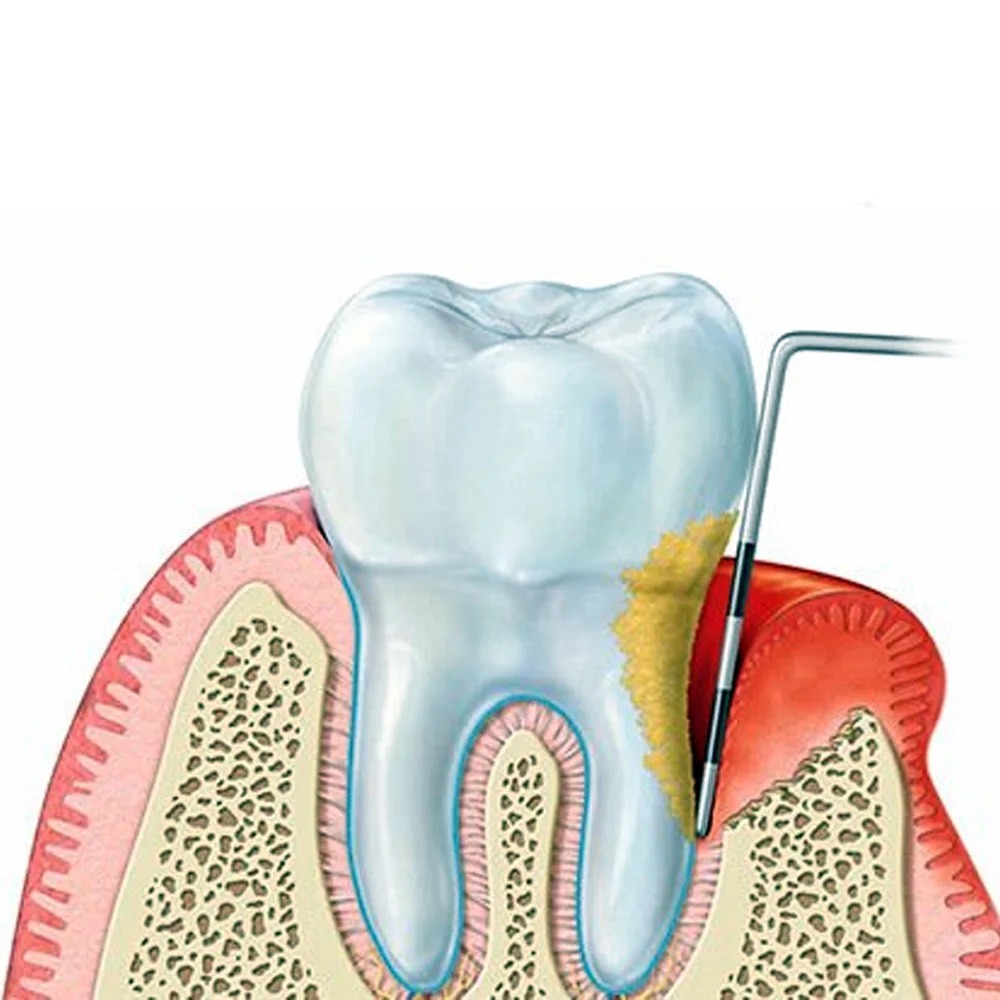

Η Περιοδοντολογία αποτελεί έναν από τους βασικότερους τομείς της σύγχρονης οδοντιατρικής, καθώς ασχολείται με τη φροντίδα και τη θεραπεία των ιστών που στηρίζουν τα δόντια: ούλα, περιοδόντιος σύνδεσμος και φατνιακό οστό.

Η ουλίτιδα είναι το πρώτο στάδιο της περιοδοντικής νόσου και προκαλείται κυρίως από την συσσώρευση μικροβιακής πλάκας. Συχνά συνοδεύεται από συμπτώματα όπως:

Η περιοδοντίτιδα είναι πιο προχωρημένη μορφή της περιοδοντικής νόσου, όπου η φλεγμονή επεκτείνεται βαθύτερα στους ιστούς που στηρίζουν τα δόντια. Εάν δεν αντιμετωπιστεί, μπορεί να προκαλέσει χαλάρωση ή ακόμη και απώλεια δοντιών.

απομάκρυνση μικροβιακής πλάκας και πέτρας κάτω από τα ούλα,